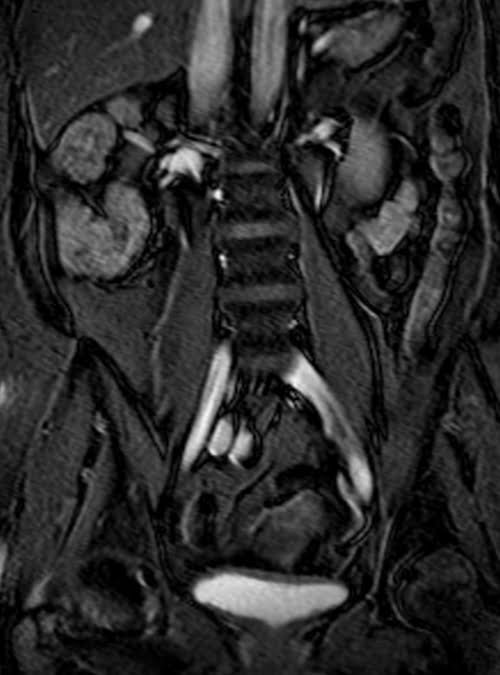

MRI kidney ureters and bladder( KUB) T2 TrueFISP fat saturated coronal images